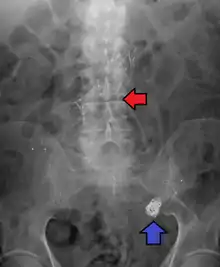

Abdominal aortic aneurysm involves a regional dilation of the aorta and is diagnosed using ultrasonography, computed tomography, or magnetic resonance imaging. A segment of the aorta that is found to be greater than 50% larger than that of a healthy individual of the same sex and age is considered aneurysmal.[9] Abdominal aneurysms are usually asymptomatic but in rare cases can cause lower back pain or lower limb ischemia.

Abdominal aortic aneurysms are commonly divided according to their size and symptomatology. An aneurysm is usually defined as an outer aortic diameter over 3 cm (normal diameter of the aorta is around 2 cm),[16] or more than 50% of normal diameter that of a healthy individual of the same sex and age.[9][17] If the outer diameter exceeds 5.5 cm, the aneurysm is considered to be large.[15]